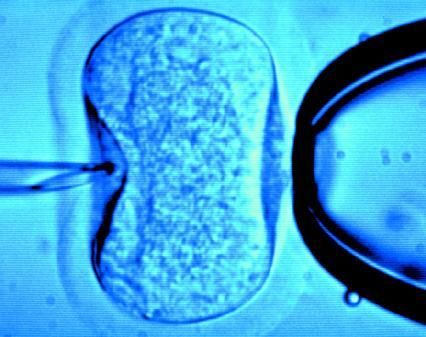

據(jù)英國(guó)《每日郵報(bào)》1月18日?qǐng)?bào)道,英國(guó)一位60歲老婦將成為英國(guó)接受試管受精最年長(zhǎng)者。這位老婦名叫蘇珊·托勒夫森,是一位退休教師,到今年10月她就滿60歲了。2008年,蘇珊曾去俄羅斯接受試管受精,在英國(guó)生下了她的第一個(gè)孩子。

倫敦哈利街的私人診所是英國(guó)試管嬰兒手術(shù)成功率較高的醫(yī)院之一,醫(yī)生們?cè)谏现芤煌鈳椭K珊·托勒夫森進(jìn)行第二次人工受孕。通常情況下,私人診所只在特殊情況下給50歲以上的婦女進(jìn)行試管受精,例如,患者仍然有月經(jīng)周期。這件事引起了絕經(jīng)后婦女是否有生育權(quán)利的倫理大討論,現(xiàn)在要求提高生育治療年齡上限的呼聲越來(lái)越高。

現(xiàn)在,蘇珊·托勒夫森一家人很幸福,丈夫尼克·邁耶是一位公司經(jīng)理,比她小11歲,他們的女兒今年2歲。專家表示,蘇珊很健康,她的女兒如果能有一個(gè)兄弟姐妹會(huì)更好,于是蘇珊想再次接受試管受精。《星期日郵報(bào)》獲悉,倫敦哈利街私人婦女診所的高級(jí)工作人員已經(jīng)同意為蘇珊做試管受精,還決定幫助另一位57歲的老婦受孕。(海瀾)